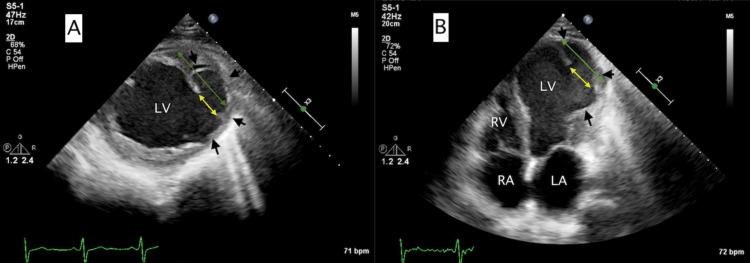

This case report delineates the clinical trajectory and management strategies of a 59-year-old Hispanic male diagnosed with a left ventricular pseudoaneurysm (LVPA) following a delayed presentation of ST-segment elevation myocardial infarction (STEMI), for which reperfusion treatment was not administered. Initially, an echocardiogram demonstrated an extensive anterolateral myocardial infarction, severe left ventricular systolic dysfunction, and an early-stage left ventricular apical aneurysm with thrombus, leading to the initiation of warfarin. Metabolic myocardial perfusion imaging via positron emission tomography indicated a substantial myocardial scar without viability, guiding the decision against revascularization. Post discharge, the patient, equipped with a wearable cardioverter defibrillator for sudden cardiac death prevention, experienced symptomatic ventricular tachycardia, which was resolved with defibrillator shocks. Subsequent imaging revealed an acute LVPA adjacent to the existing left ventricular aneurysm. Given the high surgical risk, conservative management was elected, resulting in thrombosis and closure of the pseudoaneurysm after two weeks. The patient eventually transitioned to home hospice, surviving an additional five months. This report underscores the complexities and therapeutic dilemmas in managing post-MI LVPA patients who are ineligible for surgical intervention.

本病例报告描述了一名59岁西班牙裔男性的临床病程及管理策略,该患者在ST段抬高型心肌梗死(STEMI)延迟就诊后被诊断为左心室假性动脉瘤(LVPA),未接受再灌注治疗。最初,超声心动图显示广泛前壁心肌梗死、严重左心室收缩功能障碍以及早期左心室心尖部动脉瘤伴血栓形成,遂开始使用华法林。通过正电子发射断层扫描进行的代谢心肌灌注成像显示存在大面积无存活心肌的心肌瘢痕,这为不进行血运重建的决策提供了依据。出院后,该患者佩戴了用于预防心脏性猝死的可穿戴式心脏复律除颤器,出现了有症状的室性心动过速,通过除颤器电击得以解决。随后的影像学检查显示在现有的左心室动脉瘤附近出现了急性LVPA。鉴于手术风险高,选择了保守治疗,两周后假性动脉瘤形成血栓并闭合。患者最终转入家庭临终关怀,又存活了五个月。本报告强调了在管理不符合手术干预条件的心肌梗死后LVPA患者时的复杂性和治疗困境。